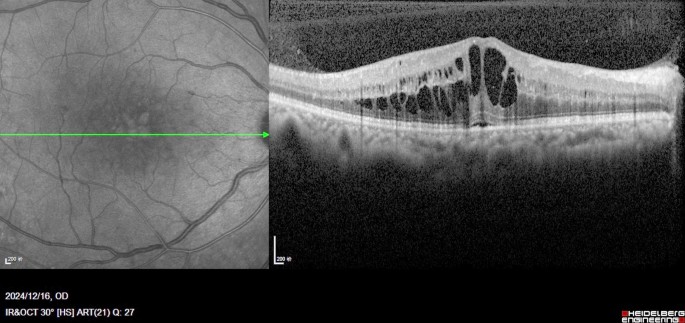

OCT images were acquired using 6-mm vertical and horizontal scans centered on the fovea in high-resolution mode with spectral domain OCT (SD-OCT, Heidelberg Spectralis OCT, Heidelberg Engineering, Germany). Recorded quantitative variables included (1) central macular thickness (CMT) and (2) the total number of hyperreflective foci (HRF) across retinal layers. Qualitative parameters were assessed for (1) size of intraretinal cysts (IRC), (2) integrity of the ELM and EZ, (3) presence of disorganization of the inner retinal layers (DRIL), and (4) presence of subfoveal fluid (SRF). All the subjects underwent examinations twice. All OCT images were analysed by the blinded retina specialist(Li-na Lv) and averages were determined. According to the TCED-HFV grading system (Table 1), the DME was divided into early, advanced, severe, and atrophic stages10 (Table 2, represented in Figs. 1, 2, 3 and 4).

Severe DME Central macrocyst surrounded by large cystoid spaces involving the outer nuclear layer, the OPL, and the INL. Severe DRIL and some hyperreflective foci are shown. The external liming membrane and the EZ are disrupted under the fovea; nevertheless, the vitreoretinal relationship is normal. The TCED-HFV grading is T = 2, C = 3, E = 1, D = 1, H = 0, F = 1, and V = 0.